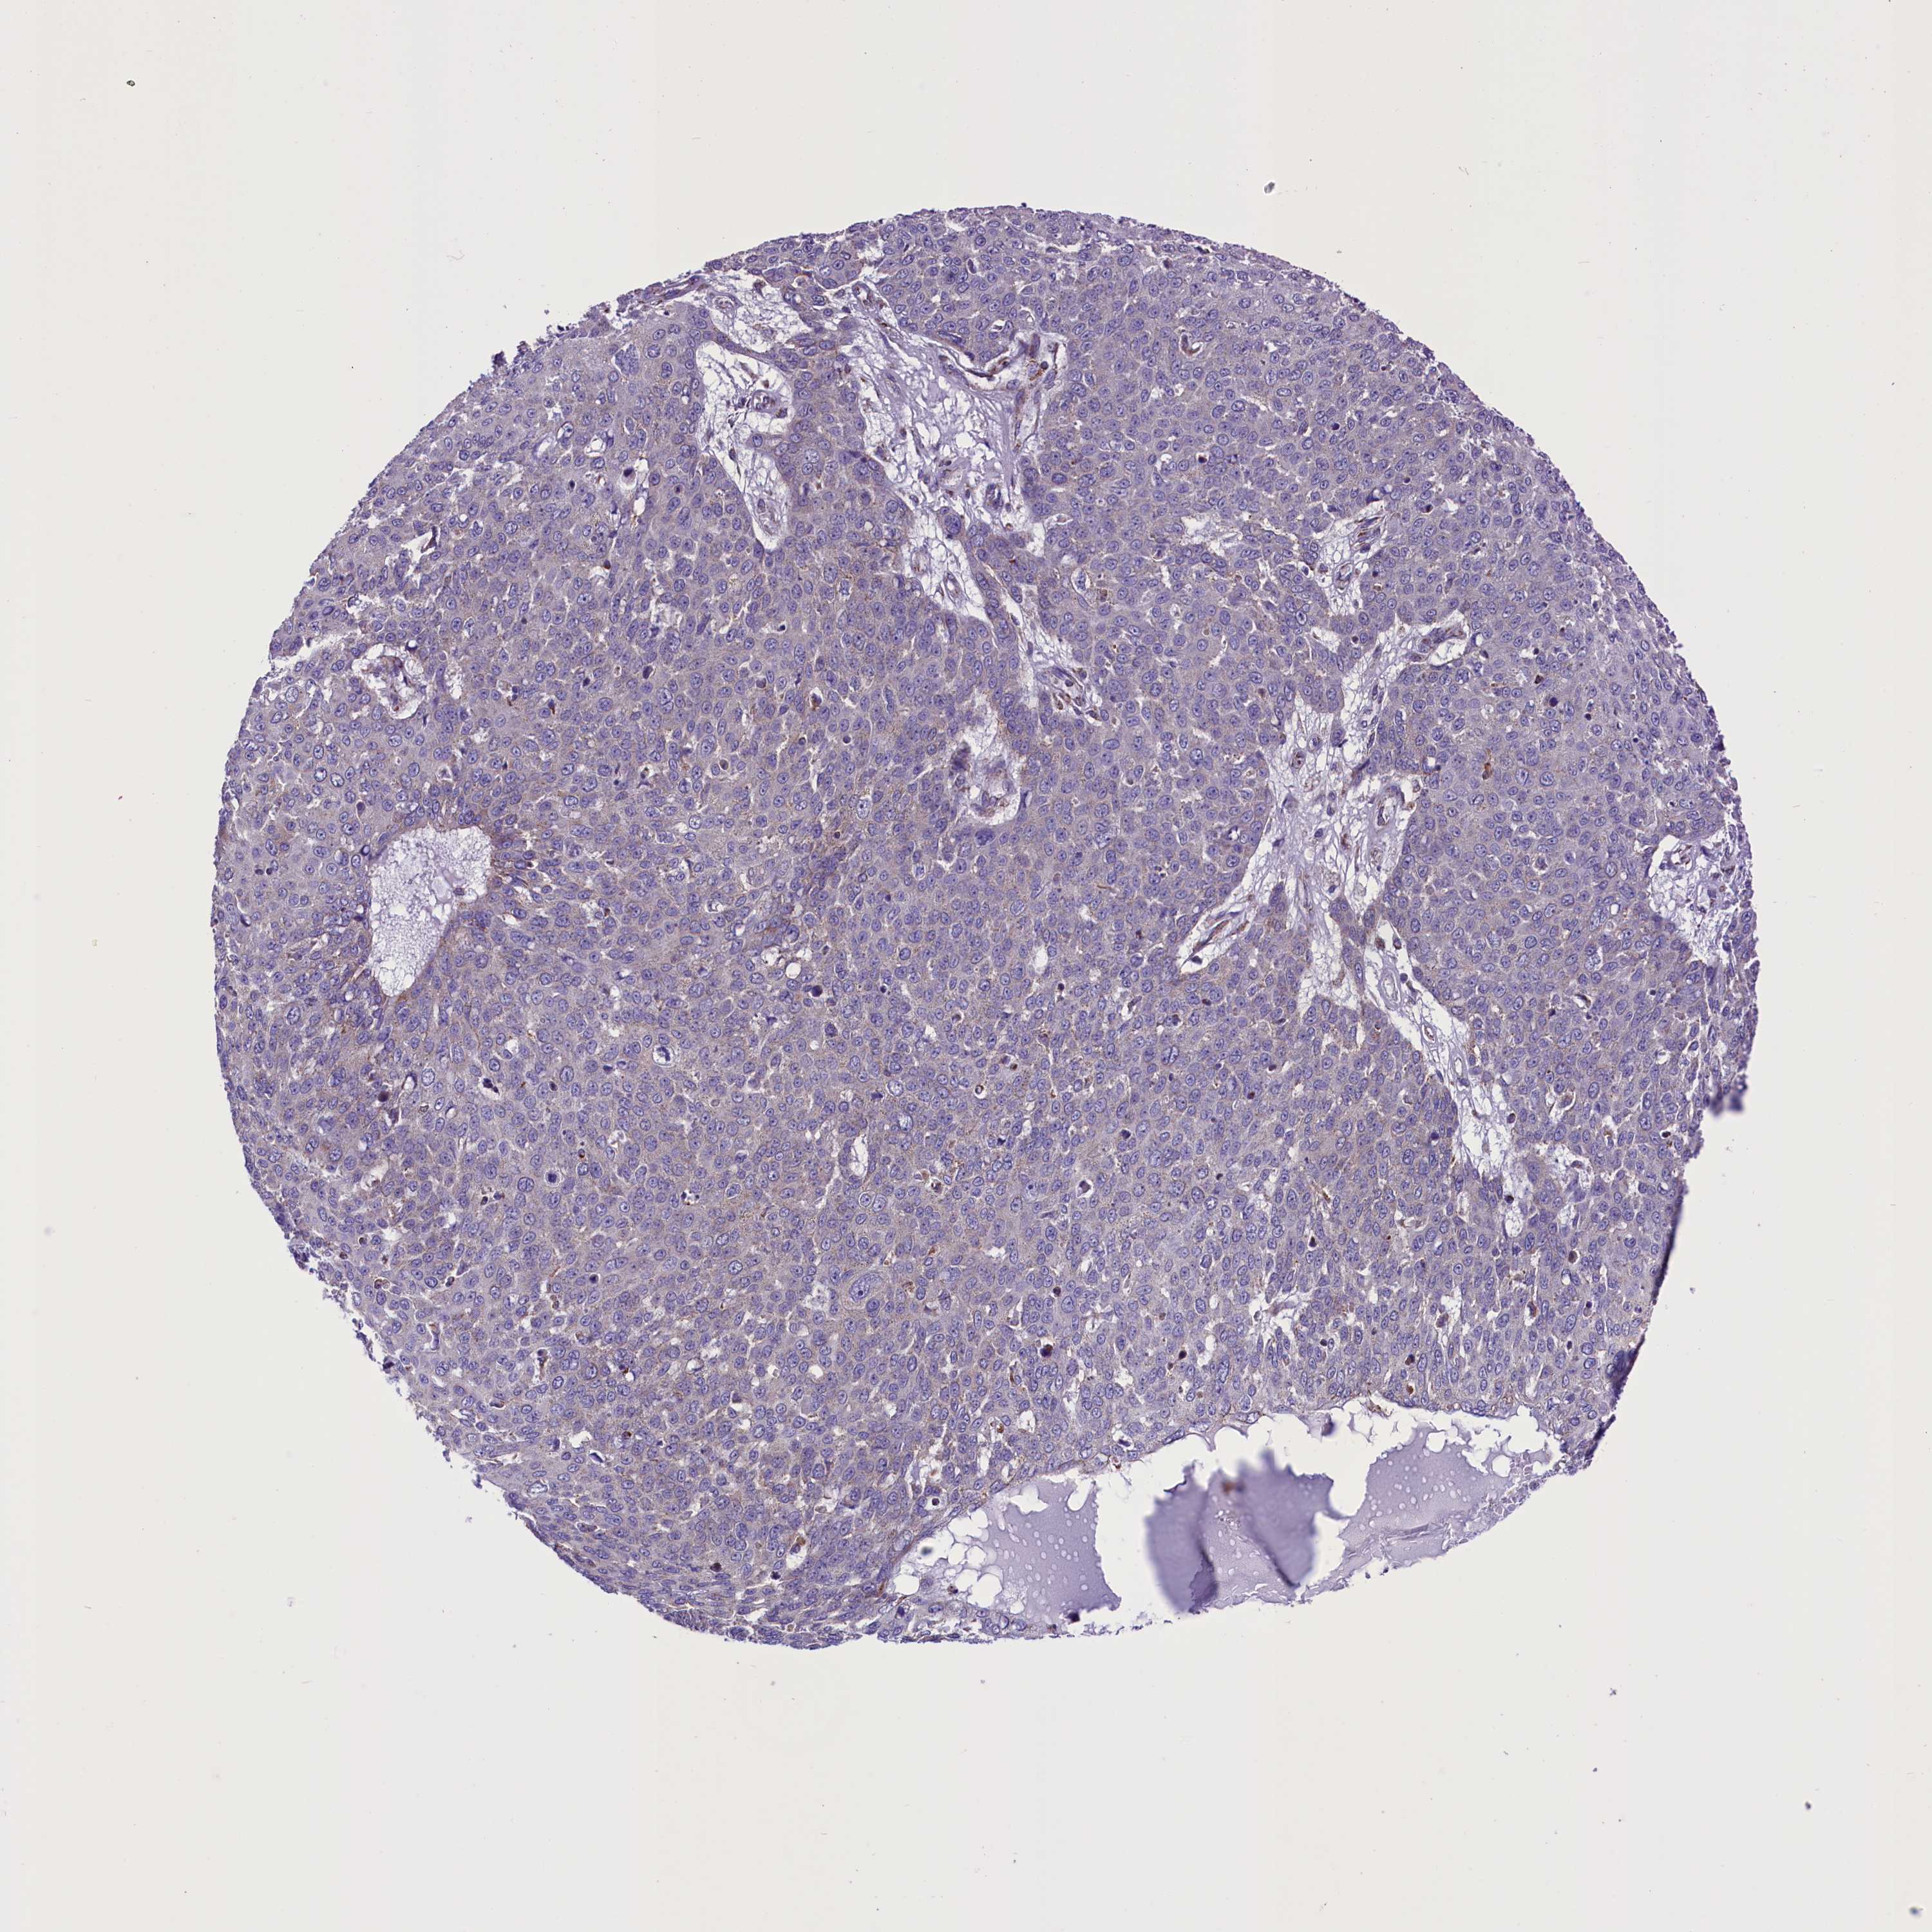

Basal cell and squamous cell cancer

SKIN CANCER - Protein expressioni

A mouse-over function shows sample information and annotation data. Click on an image to view it in a full screen mode. Samples can be filtered based on level of antibody staining by selecting one or several of the following categories: high, medium, low and not detected. The assay and annotation is described here.

Each image is clickable and will lead to virtual microscopy that enables deeper exploration of all samples and also displays staining intensity scores, fraction scores and subcellular localization as well as patient and tissue information for each sample.

Antibody HPA042507

Staining

High

Medium

Low

Not detected

Intensity

Strong

Moderate

Weak

Negative

Quantity

>75%

75%-25%

<25%

None

Location

Nuclear

Cytoplasmic/membranous

Cytoplasmic/membranous,nuclear

Basal cell carcinoma

Squamous cell carcinoma, NOS

Squamous cell carcinoma, metastatic, NOS